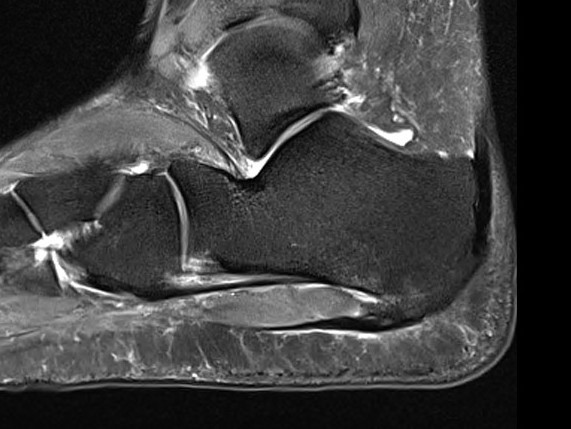

MRI

Thickened plantar fascia with tears

Exclude - retrocalcaneal bursitis / calcaneal stress fracture / Baxter's neuroma / tarsal tunnel syndrome